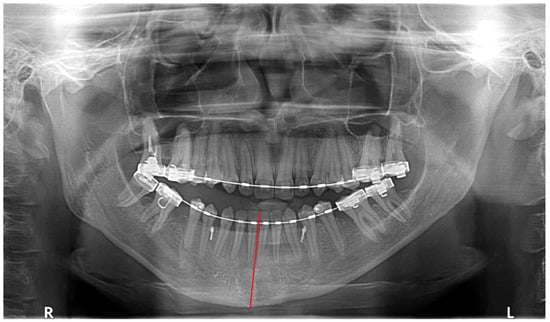

O—opposite side chin with normal position, chin shift towards the healthy side (Figure 4), chin area shifted towards the healthy side or asymmetrically overgrown on affected side;

Figure 4. Chin shifts towards the opposite side (degree of deviation marked with red line).